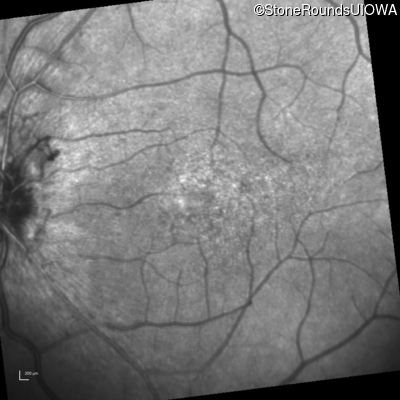

Infrared Fundus Photograph - Left - 20/60 +1

Exemplar